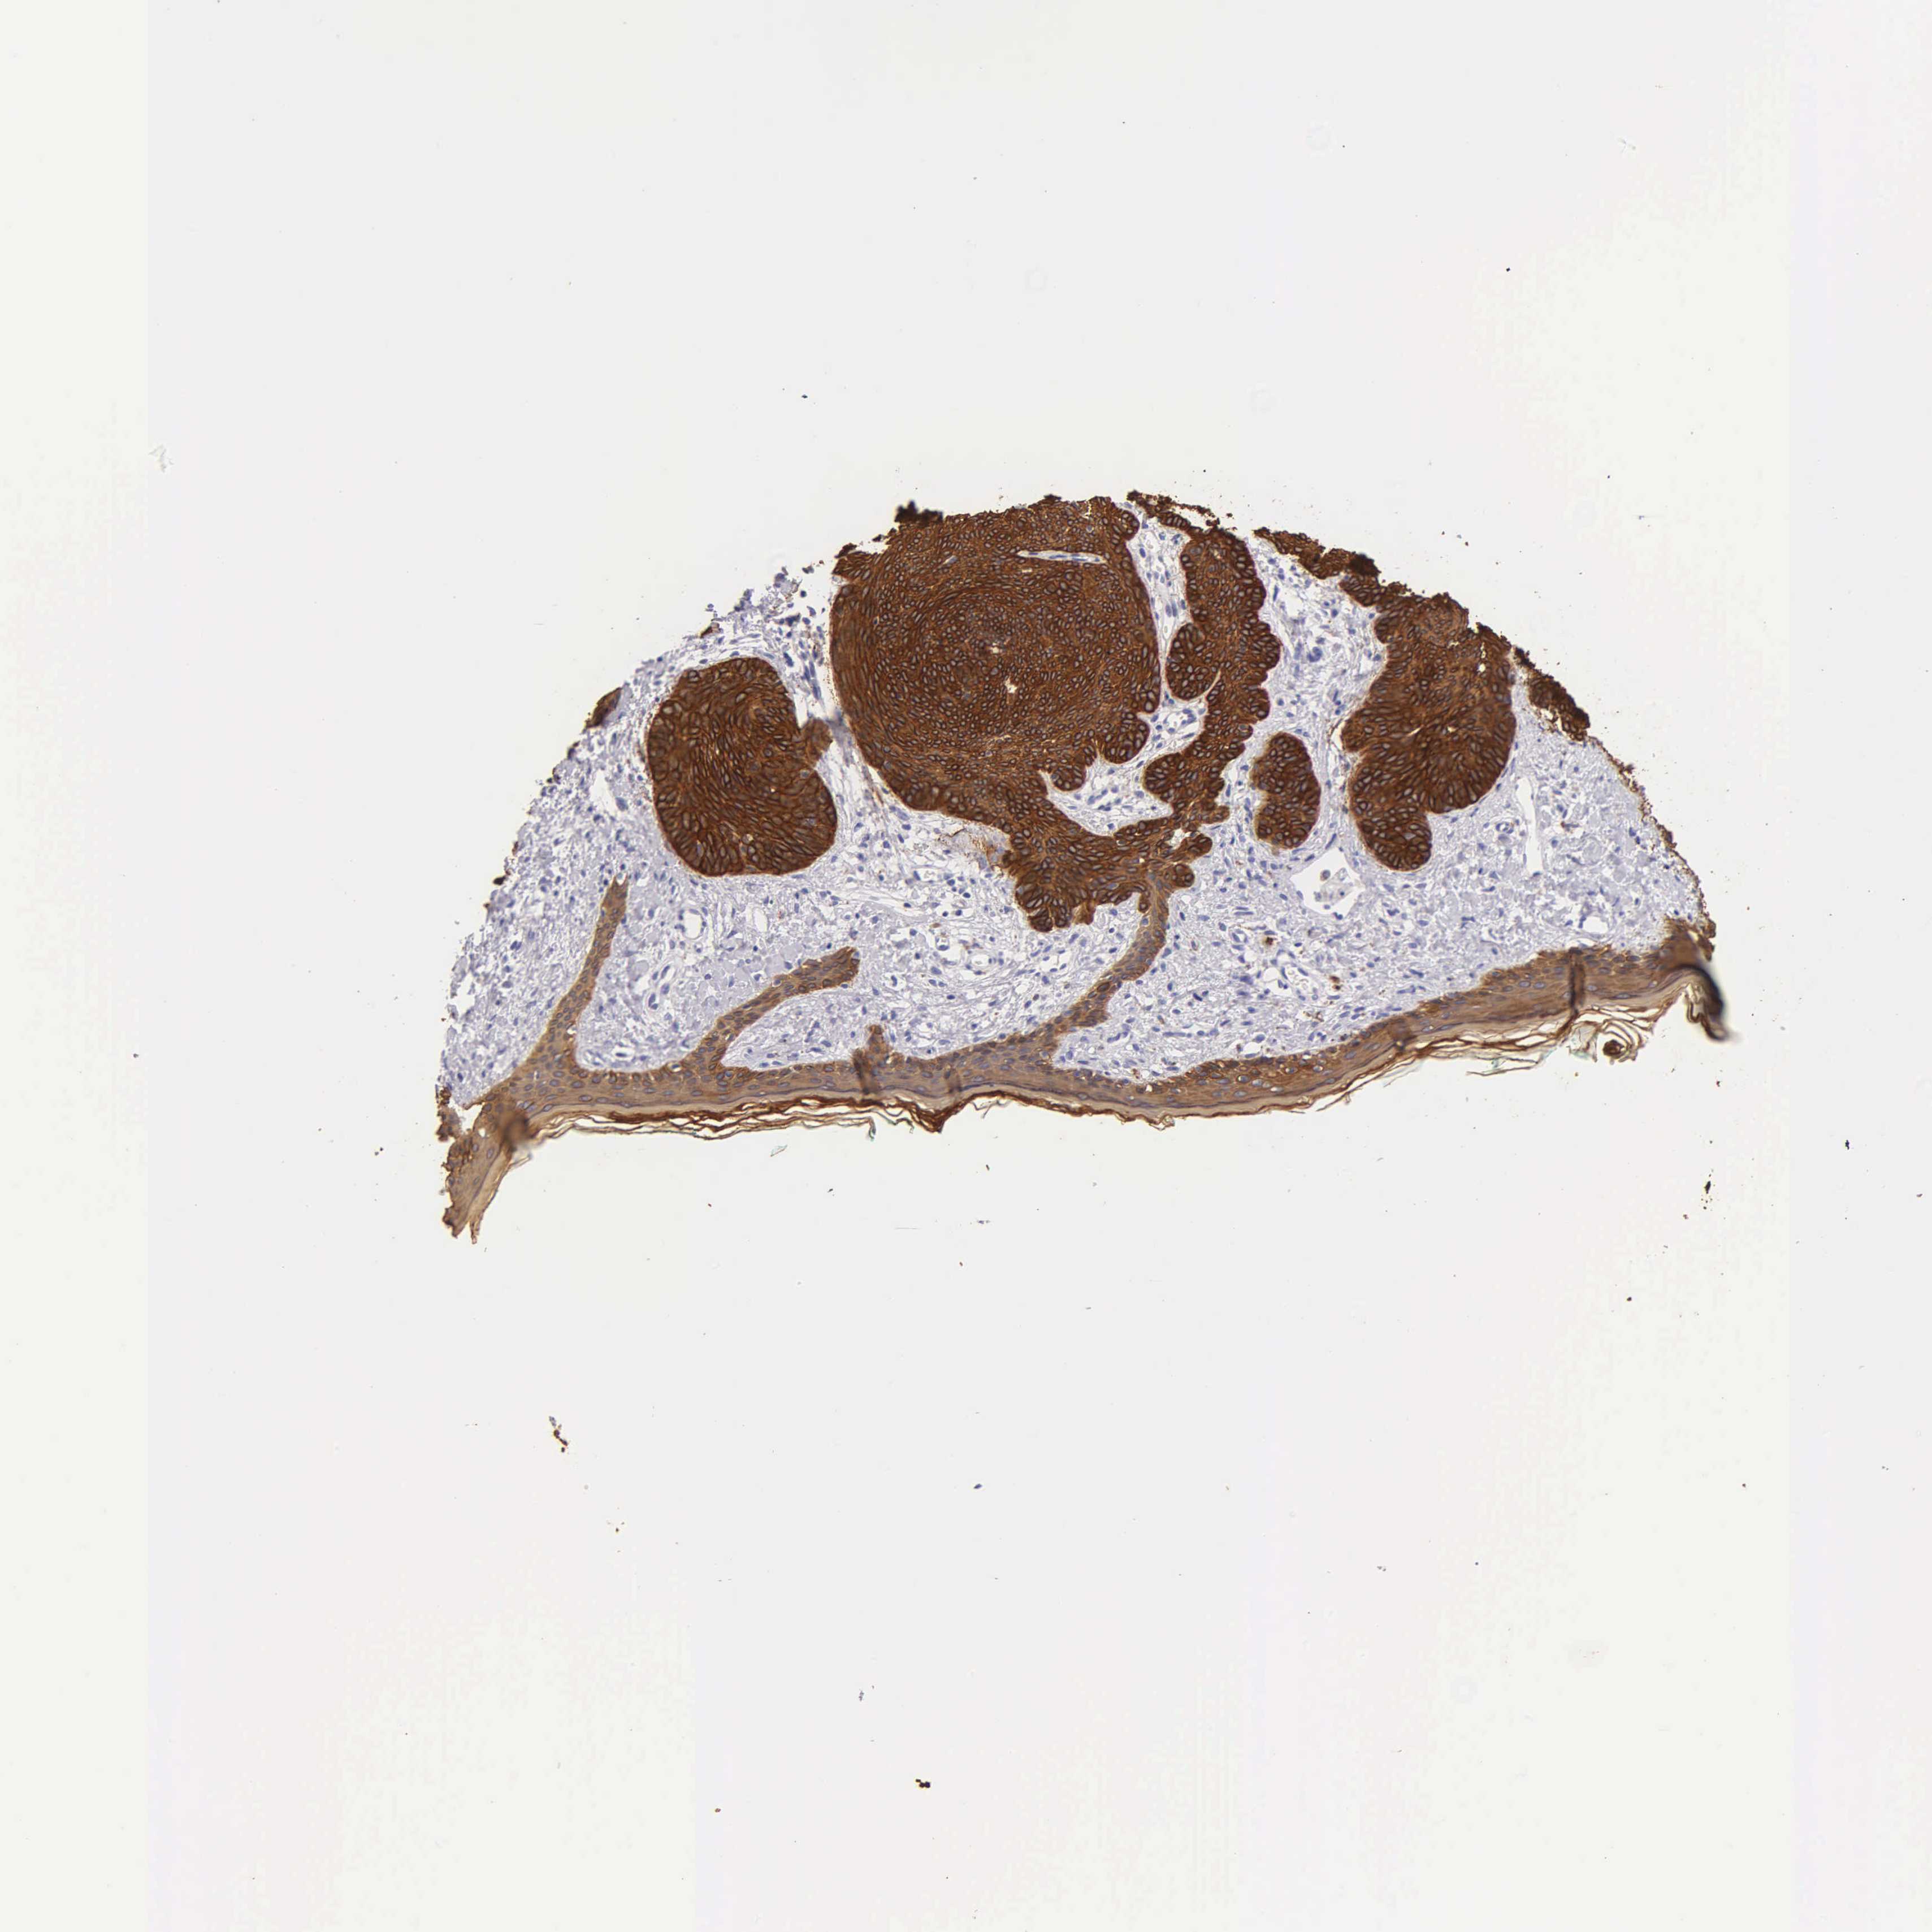

CANCER SKIN CANCER Show tissue menu

Basal cell and squamous cell cancer

SKIN CANCER - Protein expressioni

A mouse-over function shows sample information and annotation data. Click on an image to view it in a full screen mode. Samples can be filtered based on level of antibody staining by selecting one or several of the following categories: high, medium, low and not detected. The assay and annotation is described here.

Each image is clickable and will lead to virtual microscopy that enables deeper exploration of all samples and also displays staining intensity scores, fraction scores and subcellular localization as well as patient and tissue information for each sample.

Antibody HPA000452

Antibody CAB000029

Squamous cell carcinoma, NOS

Basal cell carcinoma

Squamous cell carcinoma, metastatic, NOS